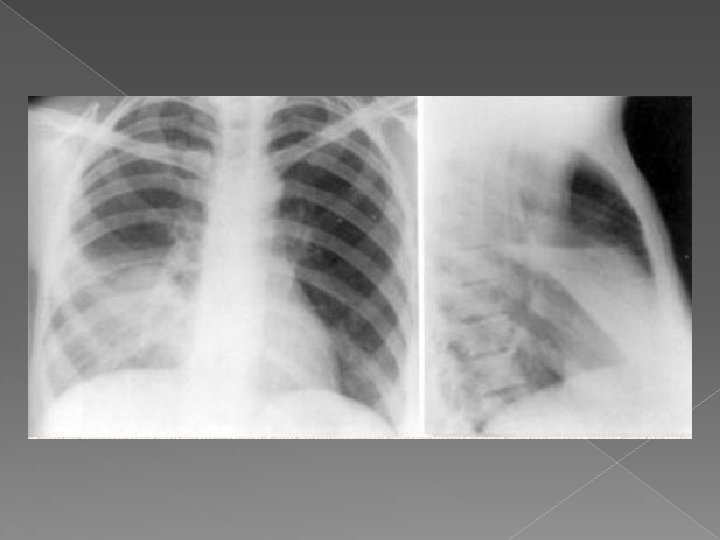

3. PNEUMONIA INTERSTIŢIALĂ Ø Peribronşică Ø Interlobulară Ø Interalveolară

Pneumonie interstitiala

TRIUNGHIUL DITTMAR RUPERT PNEUMONIE INTERSTITIALA: GRIPA opacitati hiliobazale sub forma de cordoane liniare, intre care exista opacitati nodulare si reticulare - infiltrat neomogen (“barba pieptanata”) in triunghiul hiliobazal / perihilar / intercleidohila r